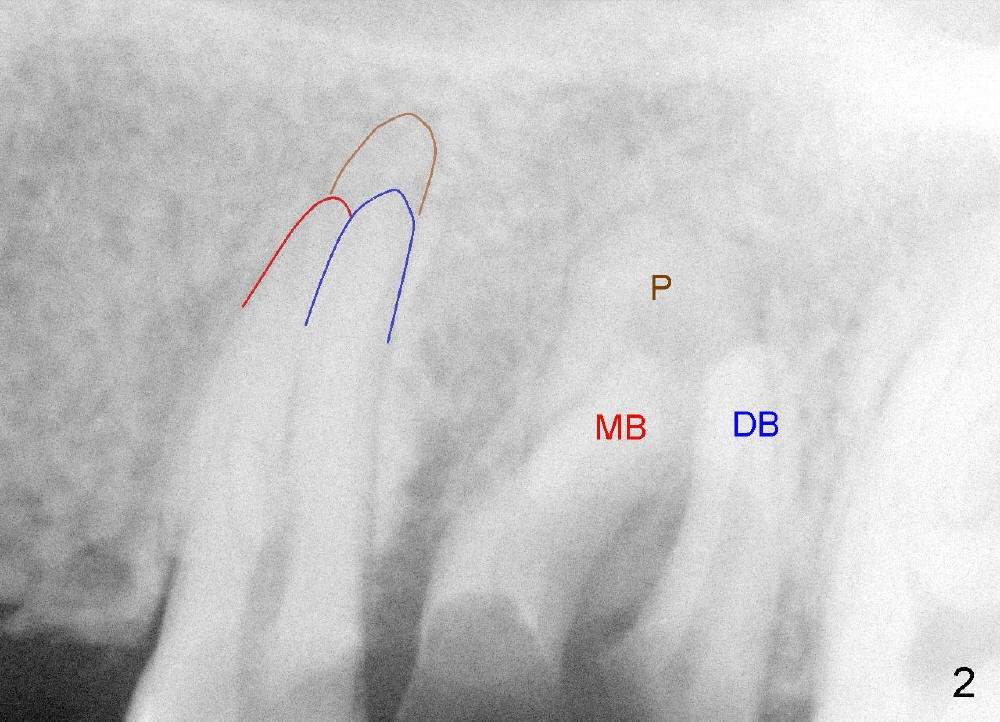

开髓时发现颊侧(图三B)髓腔比鄂侧(P)宽,根管口分布与上颌磨牙不差上下(图四),图三图四是镜影像。图五显示根管充填后:三个牙胶尖;AH26 Plus 糊剂超填(*),基本在第一磨牙牙槽窝(6)近中,第一磨牙两个月前拔除。根管治疗完成后九天糊剂(图六*)转移到第一磨牙牙槽窝远中,说明牙槽骨象蜂窝,糊剂,细菌自由来往,植牙周围不应该有感染。